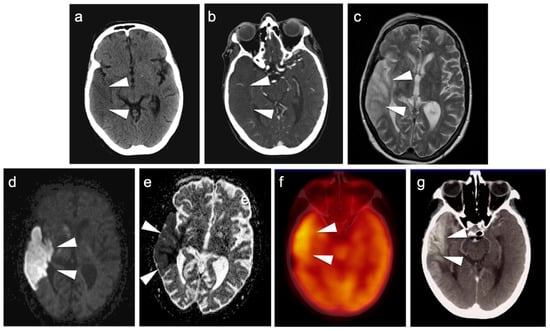

3.4. CNS Lymphoma

- Kawai, N.; Miyake, K.; Yamamoto, Y.; Nishiyama, Y.; Tamiya, T. 18F-FDG PET in the diagnosis and treatment of primary central nervous system lymphoma. Biomed Res. Int. 2013, 2013, 247152. [Google Scholar] [CrossRef] [PubMed]

- Rosenfeld, S.S.; Hoffman, J.M.; Coleman, R.E.; Glantz, M.J.; Hanson, M.W.; Schold, S.C. Studies of primary central nervous system lymphoma with fluorine-18-fluorodeoxyglucose positron emission tomography. J. Nucl. Med. 1992, 33, 532–536. [Google Scholar] [PubMed]

- Park, H.Y.; Suh, C.H.; Huang, R.Y.; Guenette, J.P.; Kim, H.S. Diagnostic Yield of Body CT and Whole-Body FDG PET/CT for Initial Systemic Staging in Patients With Suspected Primary CNS Lymphoma: A Systematic Review and Meta-Analysis. AJR Am. J. Roentgenol. 2021, 216, 1172–1182. [Google Scholar] [CrossRef]

- Marcus, C.; Feizi, P.; Hogg, J.; Summerfield, H.; Castellani, R.; Sriwastava, S.; Marano, G.D. Imaging in Differentiating Cerebral Toxoplasmosis and Primary CNS Lymphoma With Special Focus on FDG PET/CT. AJR Am. J. Roentgenol. 2021, 216, 157–164. [Google Scholar] [CrossRef]

- Mukherjee, A.; Bal, C.; Tripathi, M.; Das, C.J.; Shamim, S.A. Cerebral Toxoplasmosis Masquerading CNS Lymphoma on FDG PET-CT in Post Renal Transplant Patient. Indian J. Nucl. Med. 2017, 32, 148–149. [Google Scholar] [CrossRef]